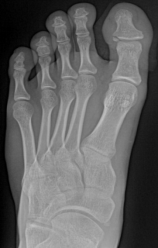

痛风

嘌呤代谢紊乱,以体液、血液中尿酸增加及尿酸盐沉着于各种间叶组织内引起炎症反应

好发于男性,发病高峰40-60岁

以第1跖趾关节最为多见

早期周围软组织肿胀,出现局限骨质硬化,晚期关节面边缘出现囊状、穿凿状骨质缺损,关节间隙可变窄,关节面不光整,晚期骨赘形成可使骨端增大

68Y,M